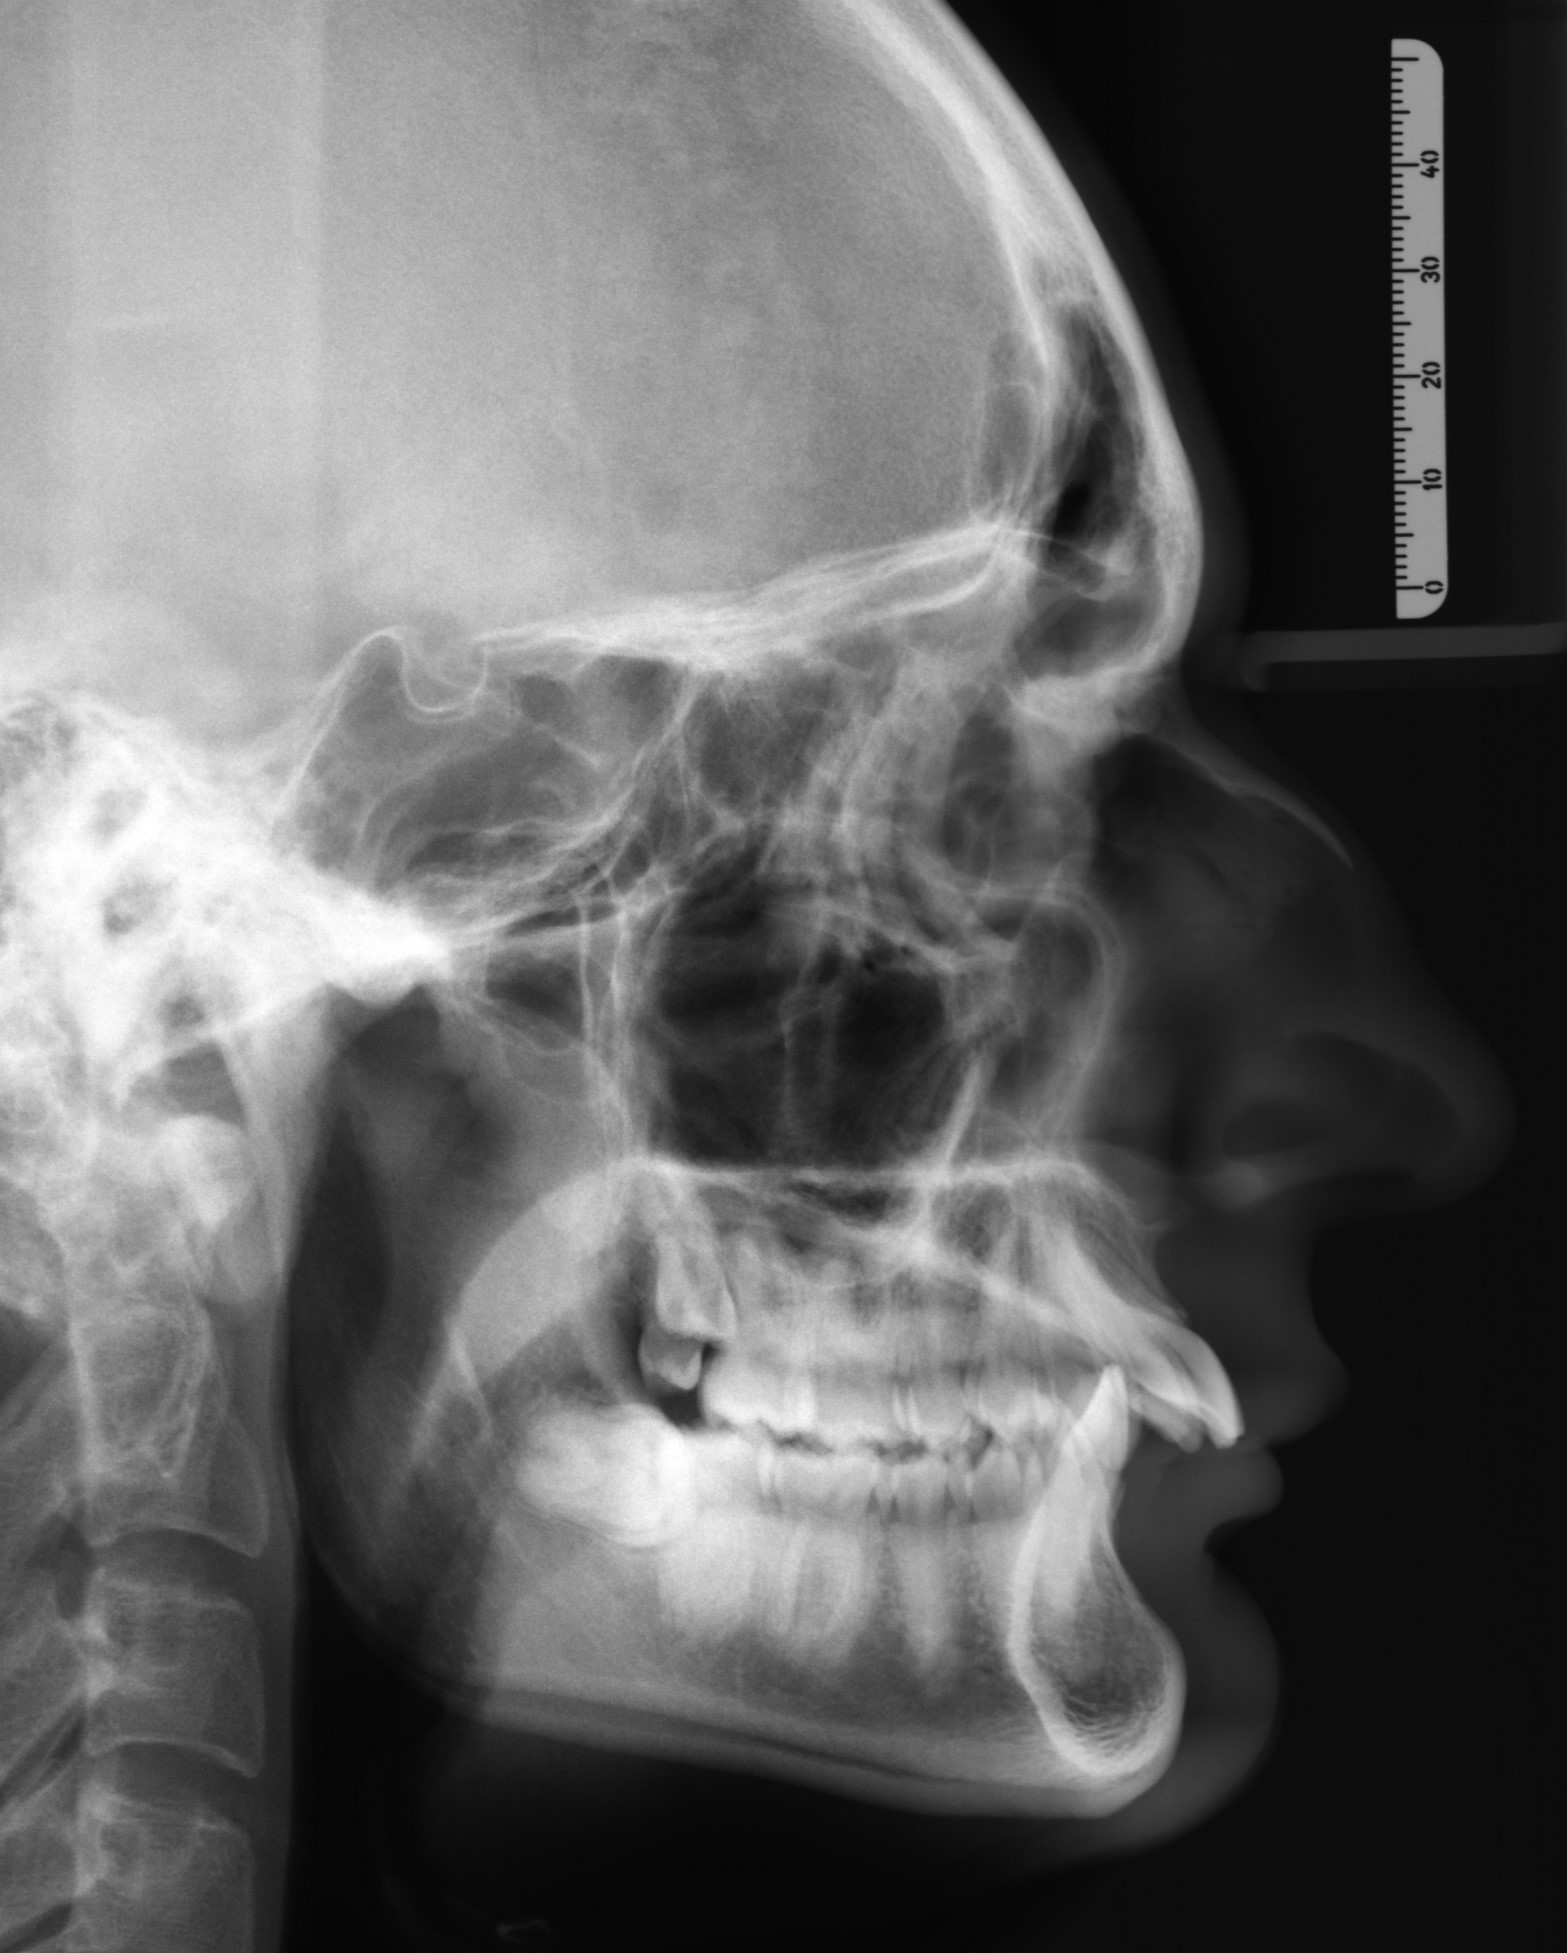

I believe I would benefit from a cw rotation + advancement of the maxilla and advancement of the mandible. Thankfully the severe overjet can be treated with braces alone, who knows, my bite may be decompensated enough that I dont even need braces after lol... anyway, my occlusion plane is way too flat, it even curves upwards it seems. Thankfully I am not downgrown, as downswung jaws are usually irrepairable even after surgery. what do you guys think?

• XRAYS.jpg